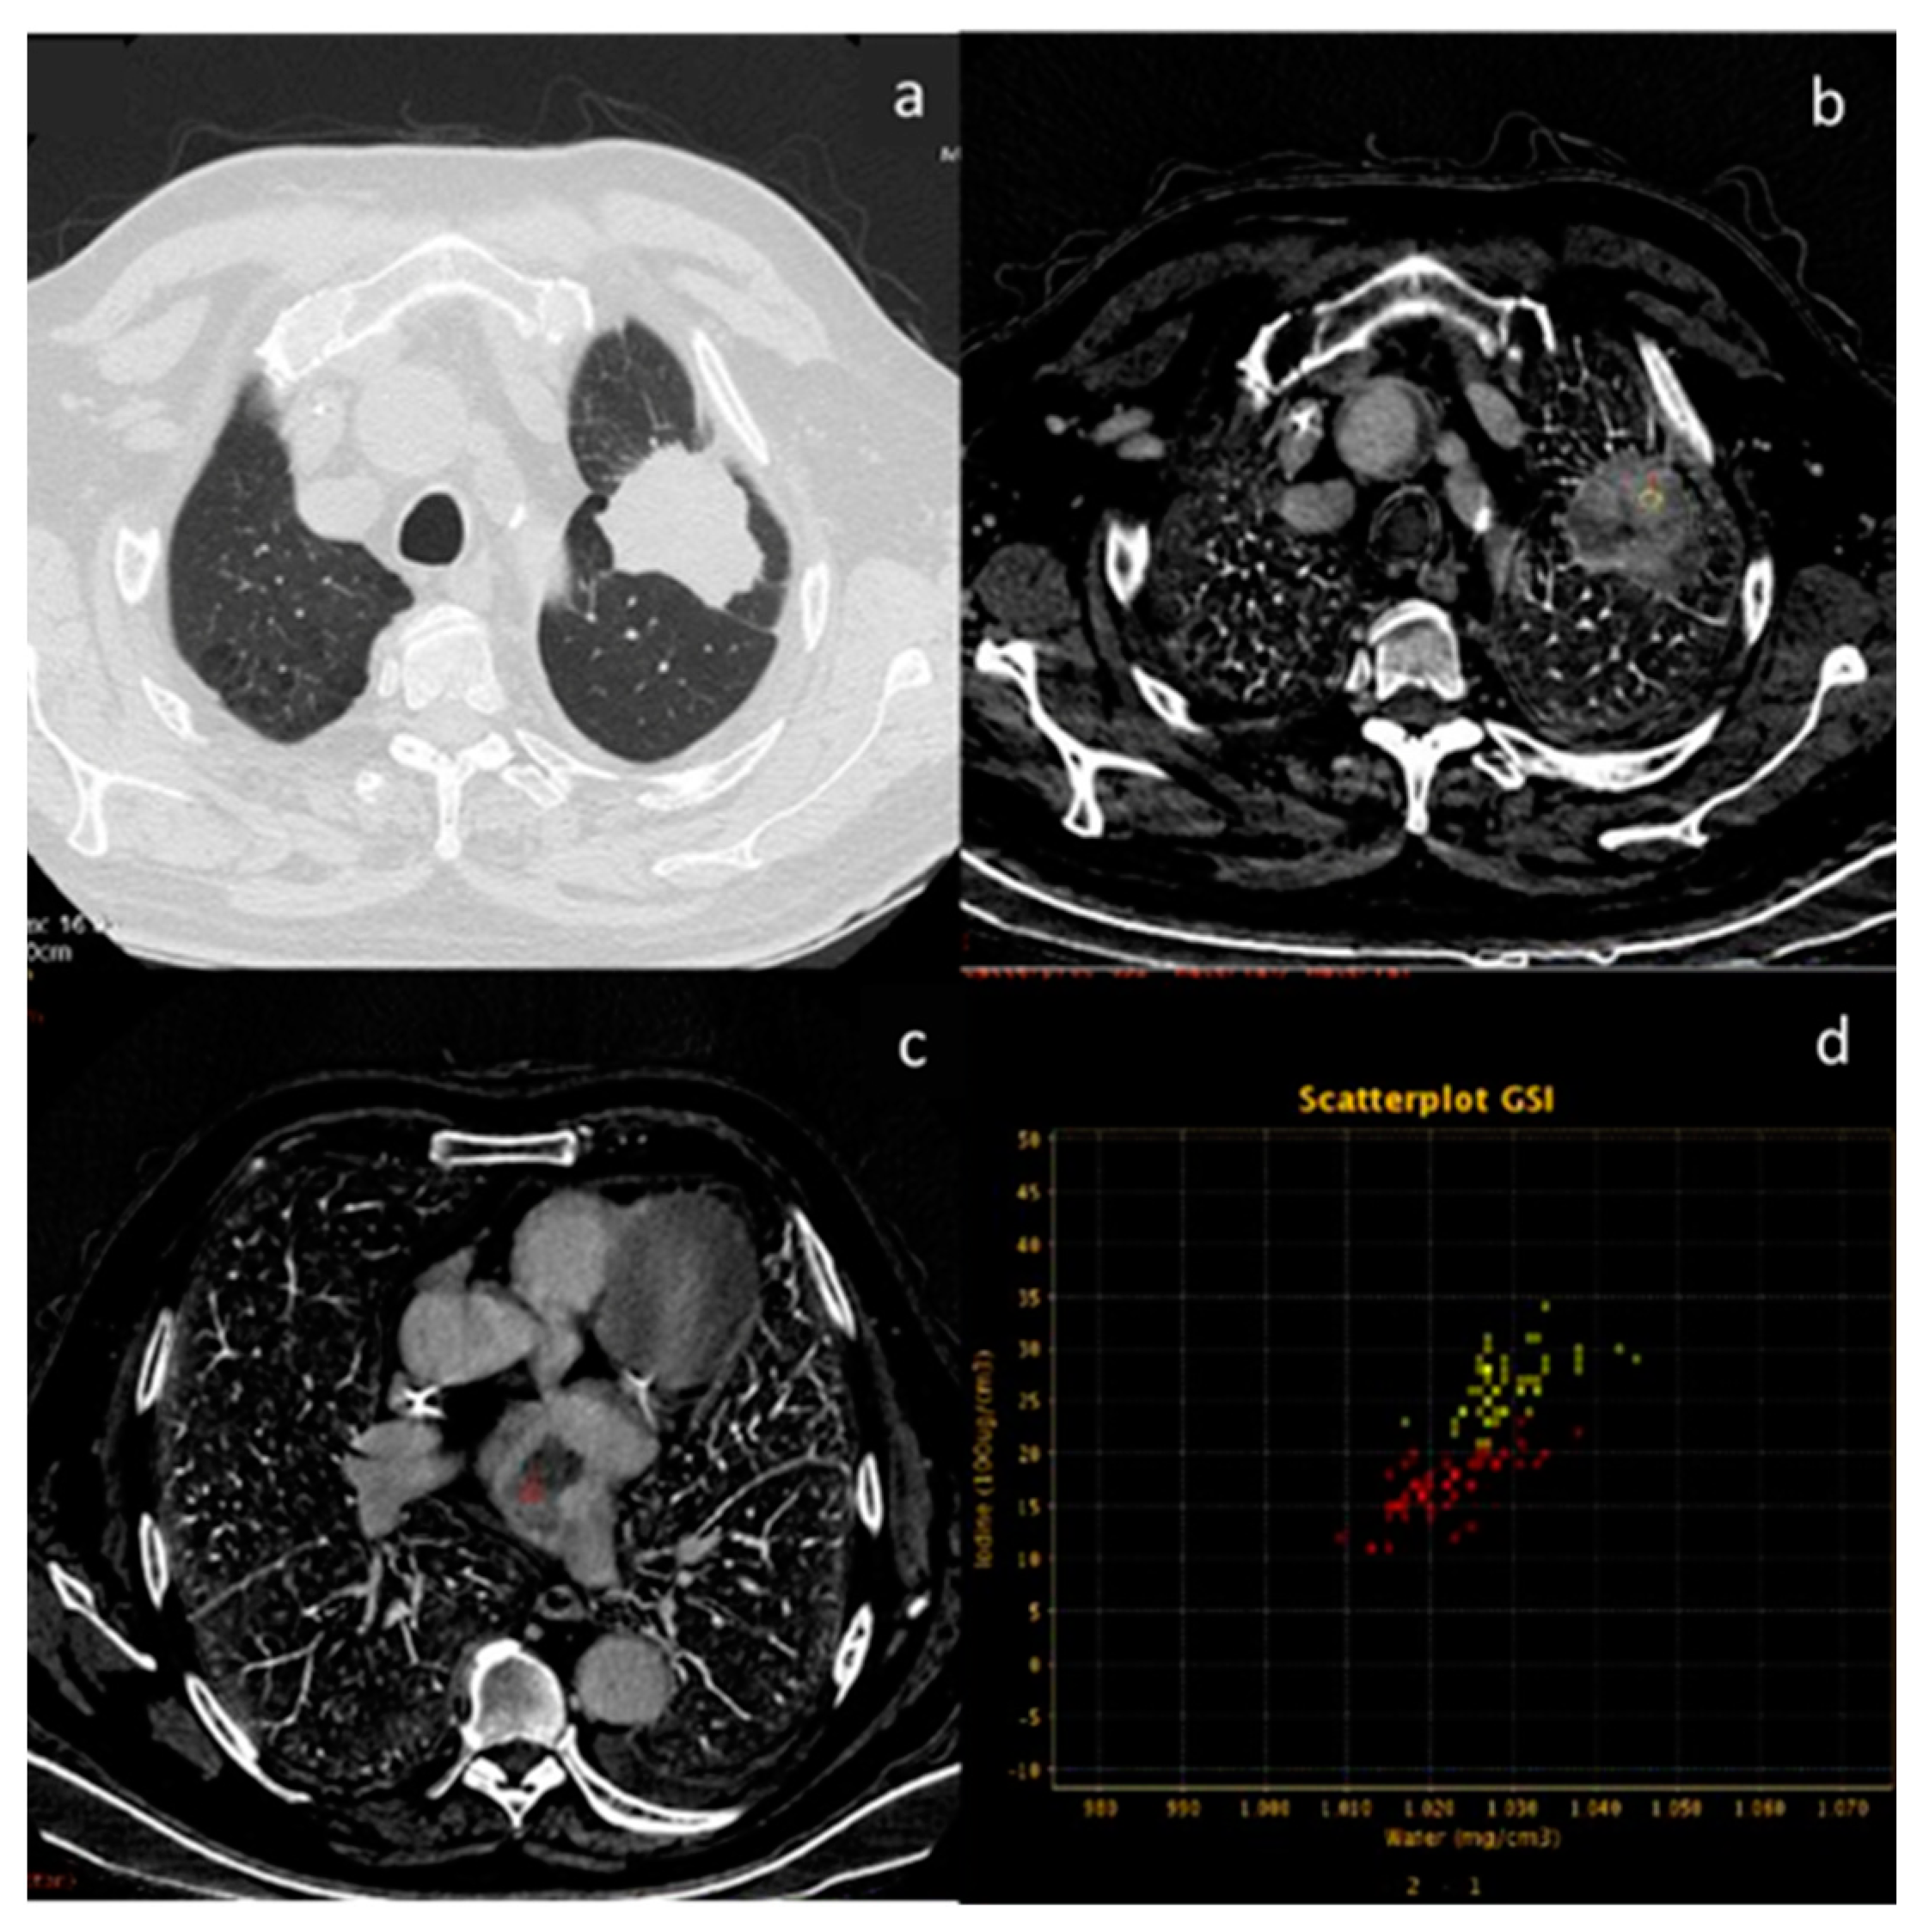

| Yan et al. [50] Multi-institutional and prospective study | China | To investigate the value of non-contrast-enhanced CT, contrast-enhanced CT, CT perfusion imaging, and dual- energy CT used for differentiating benign and malignant SPNs with a multi-institutional and prospective study | 285 | Revolution CT, GE Healthcare, Milwaukee WI, USA). No C.I. | SPNs evaluated with multimodality CT imaging contribute to improving the diagnostic accuracy of benign and malignant SPNs. DECT using the parameter of NIC at the venous phase is helpful for improving the diagnostic performance. |

- Yan, G.; Li, H.; Fan, X.; Deng, J.; Yan, J.; Qiao, F.; Yan, G.; Liu, T.; Chen, J.; Wang, L.; et al. Multimodality CT imaging contributes to improving the diagnostic accuracy of solitary pulmonary nodules: A multi-institutional and prospective study. Radiol. Oncol. 2023, 57, 20–34. [Google Scholar] [CrossRef]